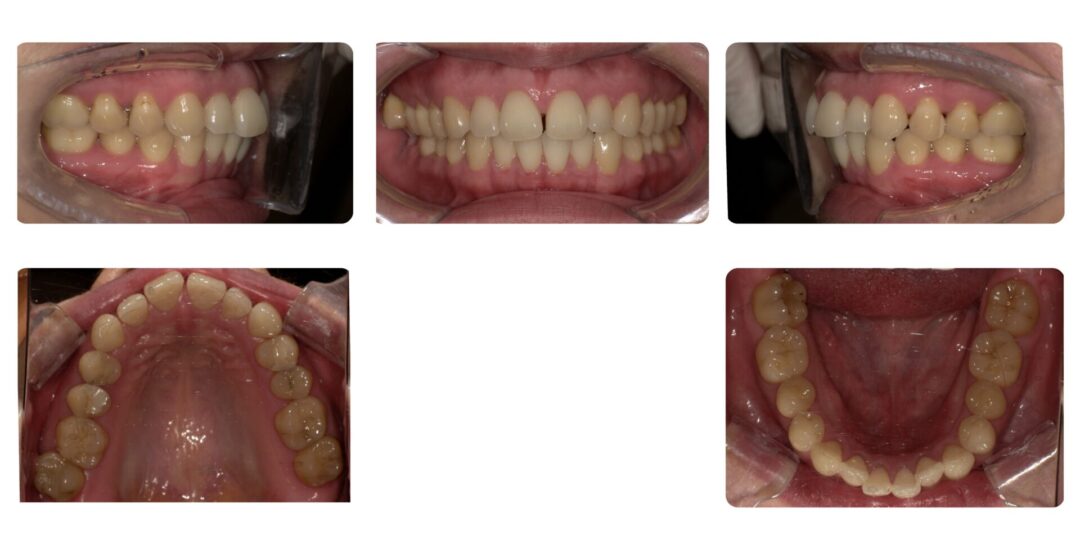

空隙歯列を伴う骨格性上顎前突|初診時38歳

矯正治療前

矯正治療後

ご相談内容

上の歯の全体的な隙間

治療内容

第二期治療 部分矯正 非抜歯 上顎6歯、下顎6歯ブラケット装置による歯列矯正

治療期間

1年1ヶ月

治療費用

自由診療 基本料金 部分矯正メタルブラケット¥330,000(初診時)、処置料¥5,500